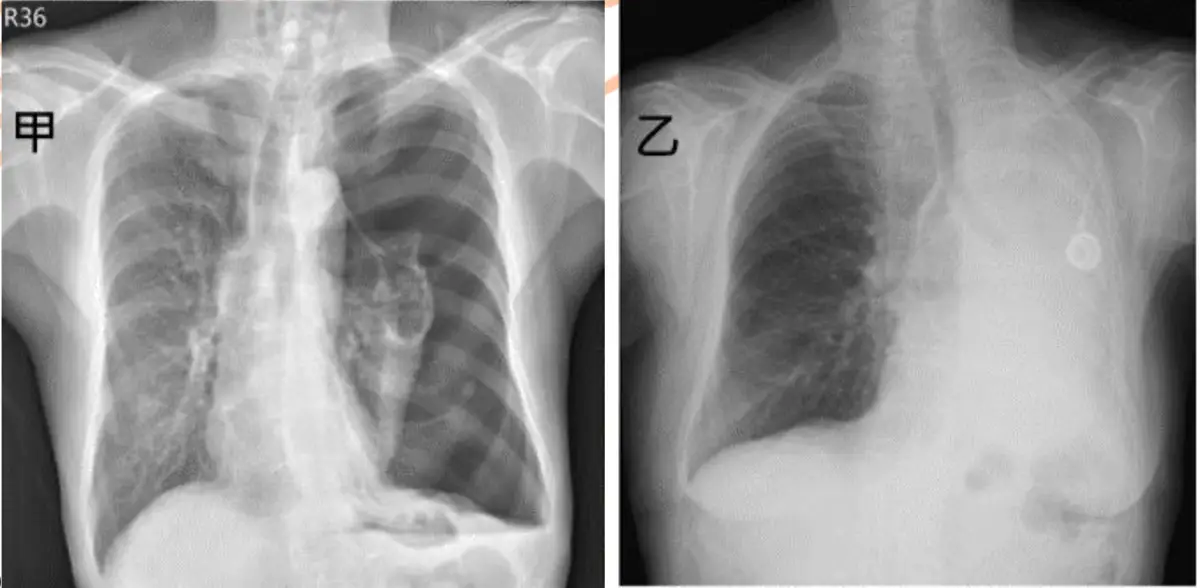

甲、乙兩位病人因呼吸喘促求診,胸部X光如圖(七)。對於是否置放胸管引流改善呼吸 喘促的決策,下列何者正確?

病人甲(左圖)

- 右側胸腔可見均勻致白浸潤陰影,下葉成本膈角鈍化呈弧形(meniscus sign),並有輕度縱隔移位至健側,提示大量胸腔積液(pleural effusion)造成肺臟壓迫及減少肺容積。

- 肺紋理上緣消失,下緣無鋸齒狀邊緣,積液層面平坦並向胸壁上緣凹向肺野,符合自由流動性積液的放射特色。

病人乙(右圖)

- 右側胸腔出現大片均勻高透亮區,內部可見稀疏不規則的肺血管紋理,有邊緣薄壁結構但缺乏清楚的胸膜線。

- 機體無明顯縱隔移位,且右側橫隔膜輪廓平直,不具氣胸常見的過度膨脹或壓迫現象;鑑別診斷為巨型肺大泡(giant pulmonary bulla)>30%半肺野體積,非真性氣胸。

- 如誤將大泡當作氣胸置管,可能引起持續氣漏或肺臟撕裂。

病人甲胸部X光呈現典型大量胸腔積液放射特徵(成本膈角鈍化、弧形液面、肺下葉壓迫、縱隔移位),對於此類大量積液合併症狀者,胸管引流為標準治療,可有效改善肺膨脹和呼吸功能(emedicine.medscape.com)。

病人乙為巨型肺大泡(≥30%半肺野,邊緣薄壁,肺紋理殘留,無典型pleural line),影像易與氣胸混淆,但若誤將大泡當氣胸置管,將增加肺組織撕裂與持續氣漏風險,乃相對禁忌症之一,不宜置管(jetem.org)。